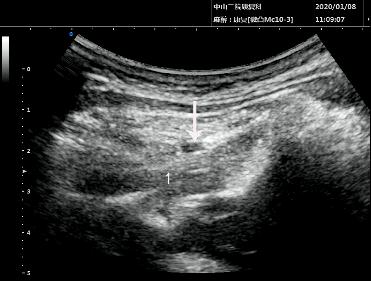

考虑到林先生这次头痛和颈痛发作疼痛剧烈,口服药物效果不显著,医生给予超声介入第2颈神经后支阻滞。

超声介入第2颈神经后支阻滞声像图(数字“1”为头下斜肌,白色箭头显示药液弥散)

超声介入第2颈神经后支阻滞是在超声介入下在头下斜肌浅层注入镇痛液,可快速、有效减轻局部炎症反应,减轻对神经卡压,从而缓解疼痛。